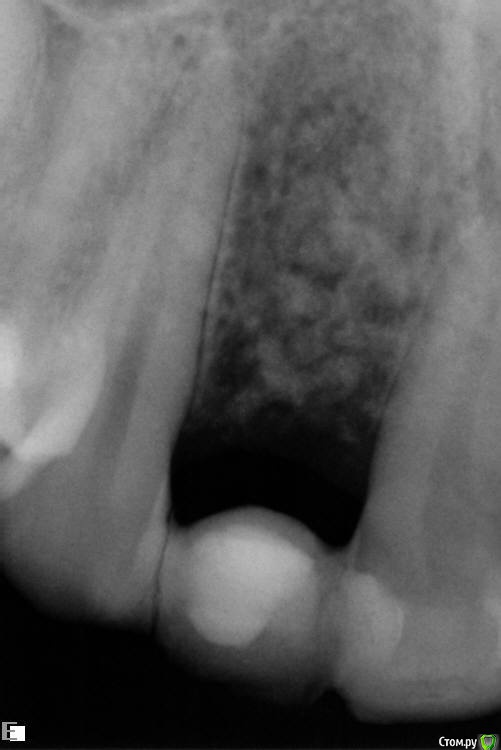

Slaggy Опубликовано 22 июля, 2016 Автор Поделиться Опубликовано 22 июля, 2016 Что за обработка лазером?Стерилизация лунки - Иногда лазером, иногда гексидином промываюЯ в это шаманство верю слабо, но "каждая мошка мяса - трошку" koreandrОтправлен 20 июля 2016 - 14:49Если выходит материал, значит есть откуда выходить. Дырка. Вот и вся биология. Через 2 месяца после операции дырок быть не должно в идеале. Вот и я о том - где мембран и периост? фоты нашел преоп и на момент фэйла снимок и фото Ссылка на комментарий

Slaggy Опубликовано 15 августа, 2016 Автор Поделиться Опубликовано 15 августа, 2016 (изменено) Тут просили картинки-20/05,2016 , 15/08,2016 Графт продолжает всплывать через слизистую, хрустит при пальпации области аугментации Почистил слизистую от графта, дам паузу 2 недели и вычищаю все начисто. Изменено 15 августа, 2016 пользователем Slaggy Ссылка на комментарий